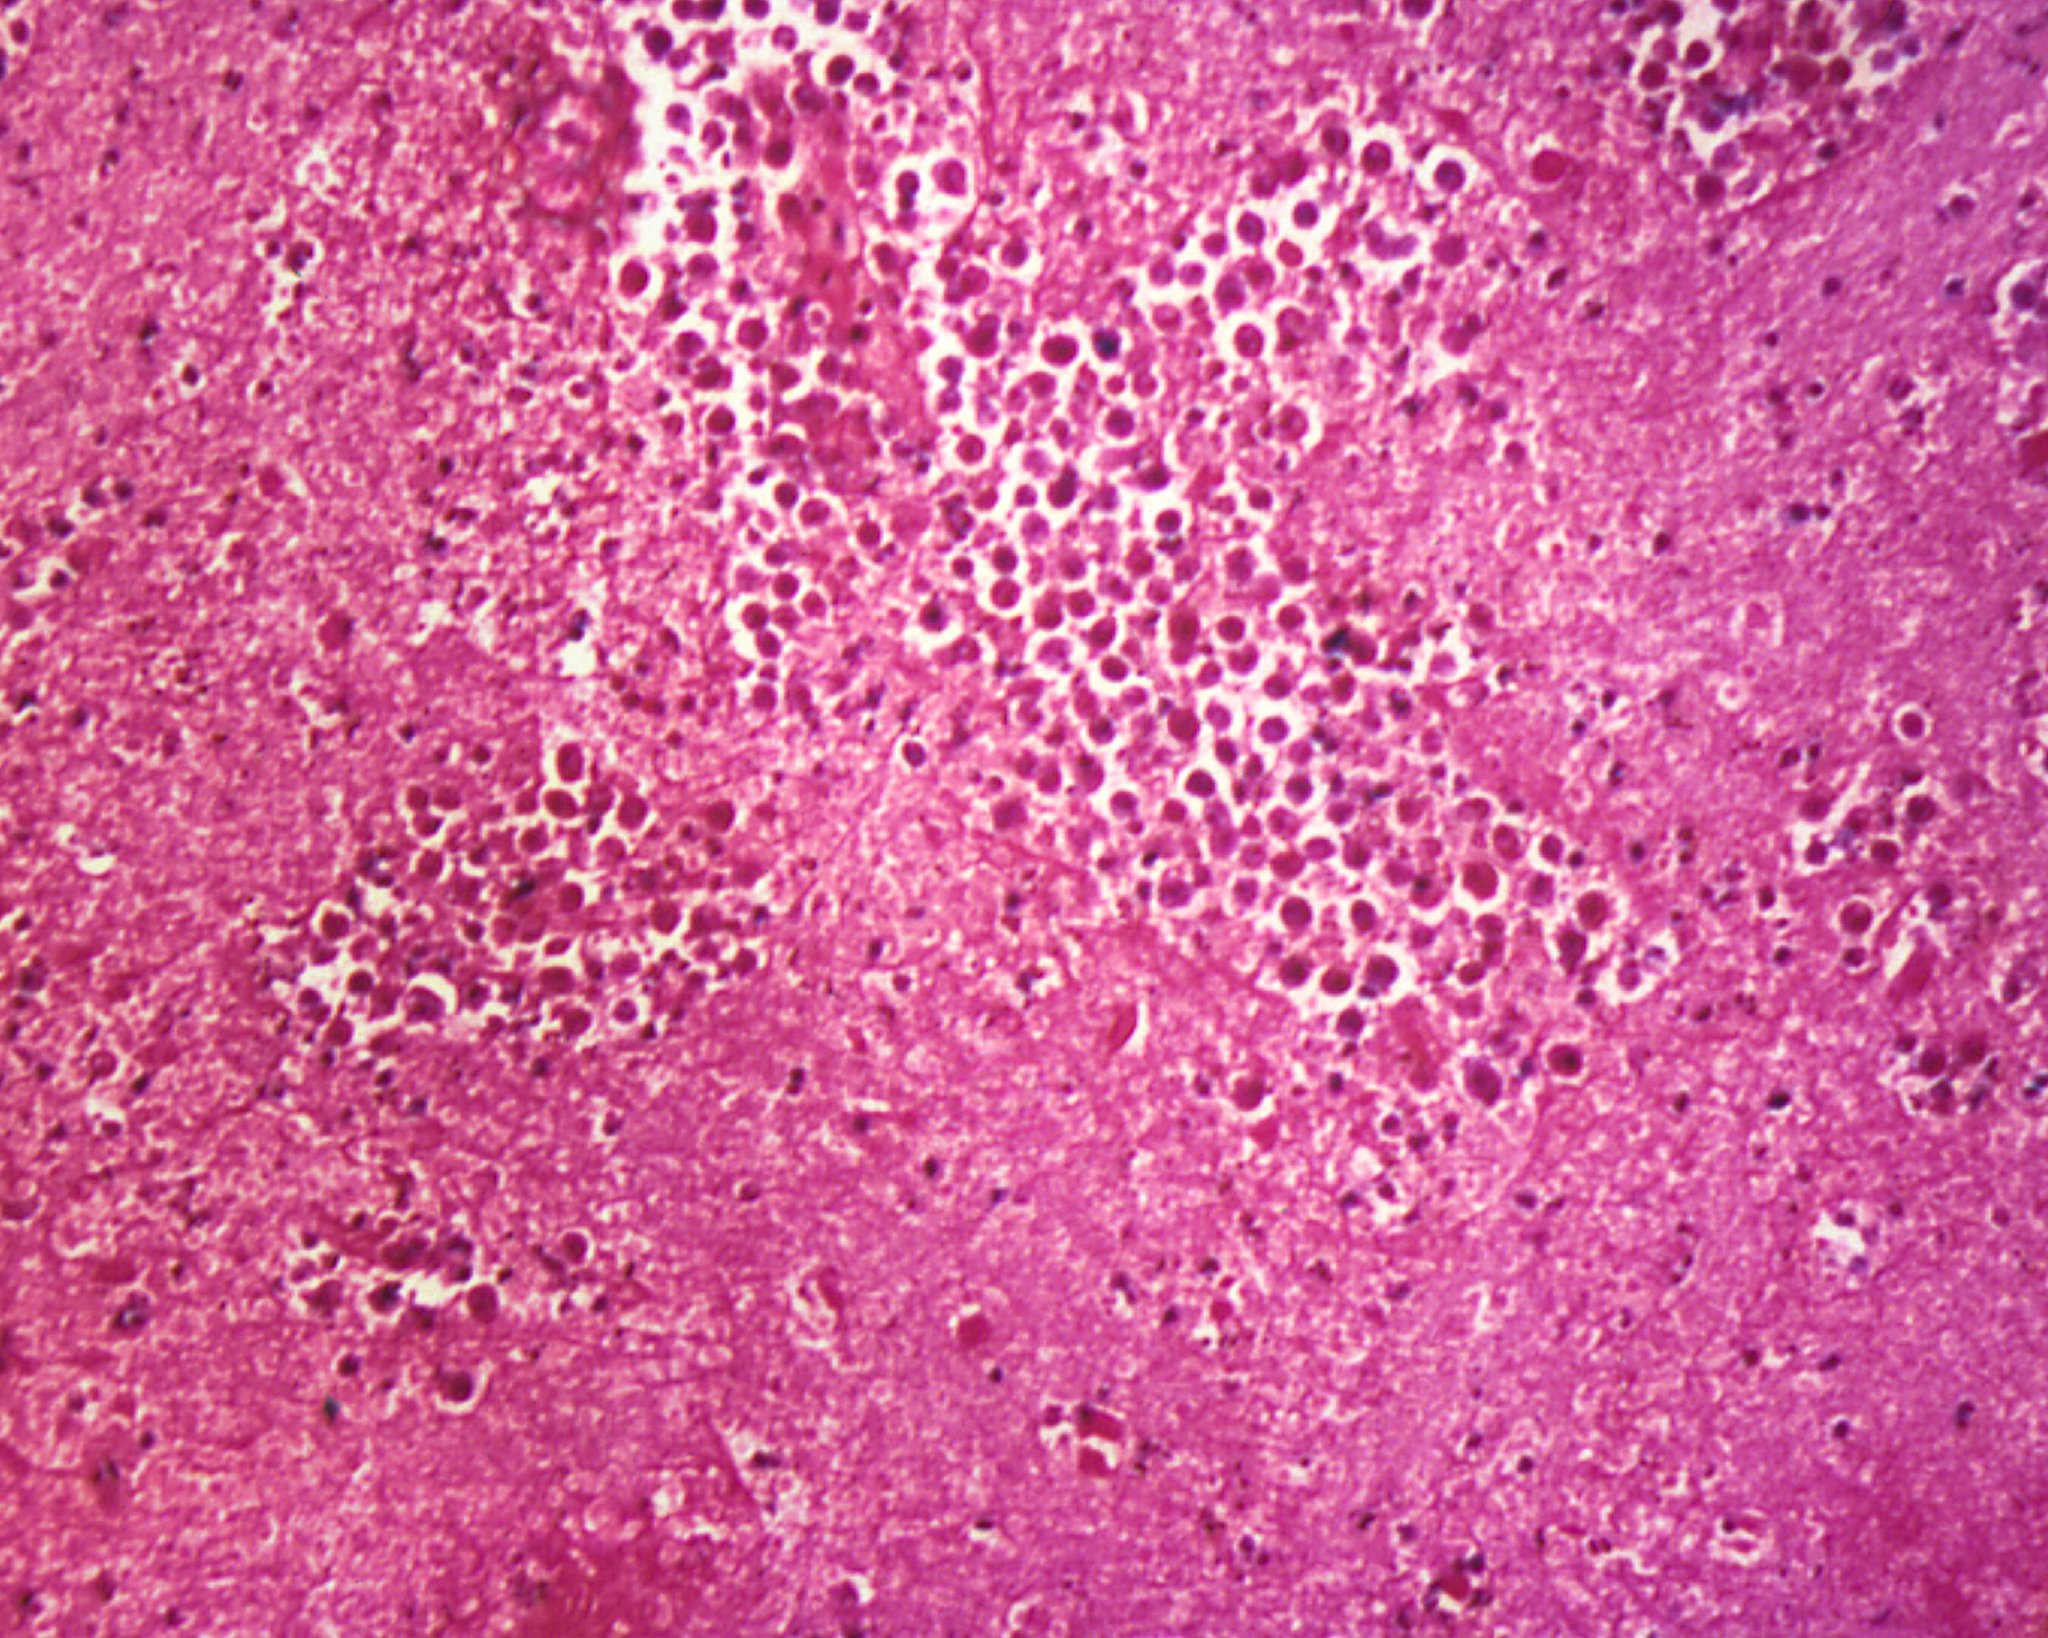

Nákazlivé ochorenie primárnej amébovej meningoencefalitídy, ktorému podľahol 11-ročný chlapec z Plaveckého Štvrtka, spôsobuje smrtiaci parazit slzovičkovka zhubná. Ide o amébu z rodu Naegleria, konkrétne o zriedkavý mikroorganizmus Naegleria fowleri.

Ochorenie je veľmi vzácne, ale úmrtnosť vysoká - celosvetovo až 97 percent.

Tento parazit sa vyskytuje v teplých sladkovodných prostrediach, ako sú jazerá, rieky či prírodné nádrže. Vyhovuje mu teplota 35 až 45 stupňov Celzia. „Vo výnimočných prípadoch túto amébu zaznamenali aj v umelých bazénoch s nedostatočnou úpravou vody a technickou údržbou,“ špecifikuje pre Štandard Úrad verejného zdravotníctva SR.